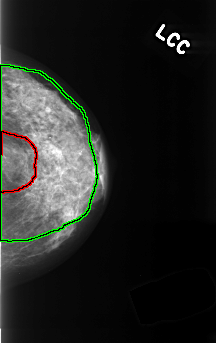

C_0366_1.LEFT_CC

FILE: C_0366_1.LEFT_CC.OVERLAY

TOTAL_ABNORMALITIES 2

ABNORMALITY 1

LESION_TYPE MASS SHAPE ROUND MARGINS ILL_DEFINED

ASSESSMENT 4

SUBTLETY 4

PATHOLOGY BENIGN

TOTAL_OUTLINES 1

BOUNDARY

ABNORMALITY 2

LESION_TYPE CALCIFICATION TYPE PLEOMORPHIC DISTRIBUTION DIFFUSELY_SCATTERED

ASSESSMENT 3

SUBTLETY 3